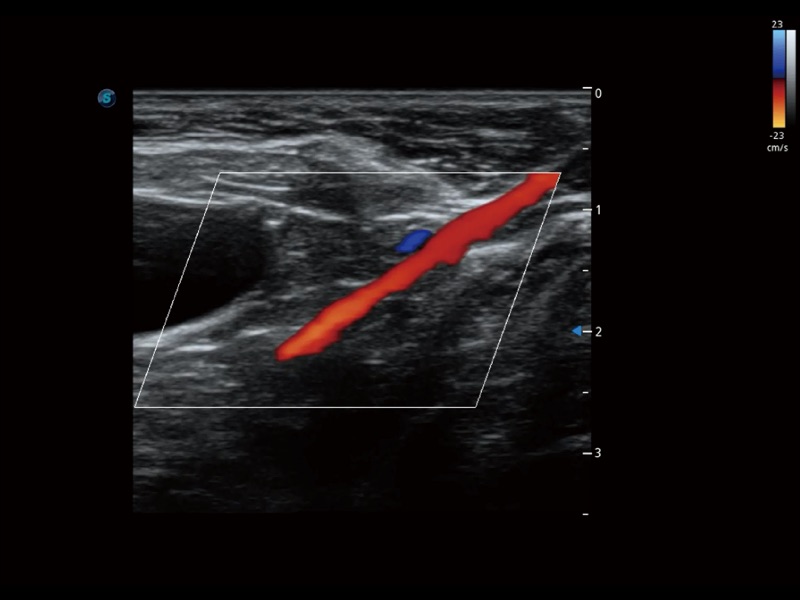

• Micro F 显微血流成像

通过创新的 Matrix E自适应滤波器和超长时间域算法,极大提升超低速微细血流的检出能力,同时更精准地滤除软组织和噪声信号,为兽用医生提供以往无法通过常规血流获得的疾病诊断信息。

• 宽景成像

通过色彩血流和实时宽景相结合,可观察到完整的静脉或动脉的血流,方便医生检查。实时扫查过程中,如有任何操作失误也可以很容易地进行回扫擦除,而不会中断扫查。

(犬)髂动脉血流